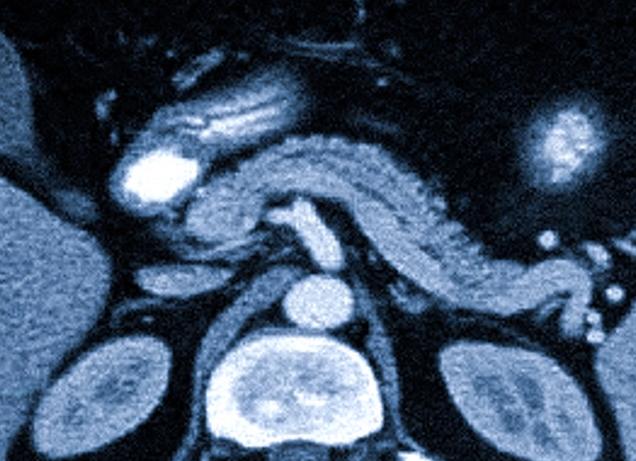

Размеры поджелудочной железы в норме головка тело хвост